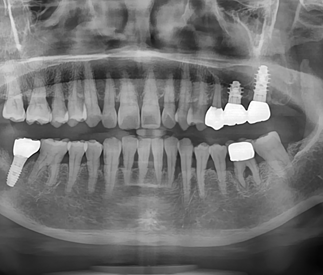

Intraoral photograph and periapical radiograph after final restoration

1 month follow-up showing stable soft tissue and well-maintained implant restorations.